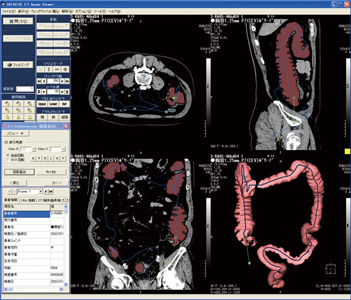

CT Colonoscopyは,解析したい腹部領域のCT画像を読み込むと,自動的に3D画像の作成と大腸領域の認識を実行する。認識結果領域の確定/解除は,3D画像上で部位を直接クリックするだけで可能である。

また,大腸領域の経路については,MPR像上で経路算出開始点と算出方向を設定するだけで算出され,結果は3D画像上に表示される(図1右下)。

図3に示す3D-MPR表示モードは,大腸管腔外組織を観察する場合に適している1)。この表示モードでは大腸内部のみが3D画像であり,その周囲はMPR像である。この融合画像によって,ポリープなどの突起物の内部構造観察と,仮想内視鏡画像である3D画像の同時観察が行える。仮想内視鏡画像と3D-MPR像は,図1の右下の位置に表示され,どの位置で大腸内部を観察しているかは,3つのMPR画面によってガイドされる。

図1 CT Colonoscopy